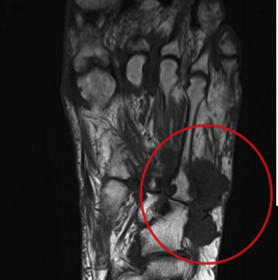

| What does this indicate? | Increased signal and enhancement of the soft tissue plantar to the proximal phalanx suggestive of subcutaneous infection without abscess |

| What does this indicate? | Increased signal and soft tissue distension dorsally representing subcutaneous abscess communicating with associated with plantar ulcerative defect. |